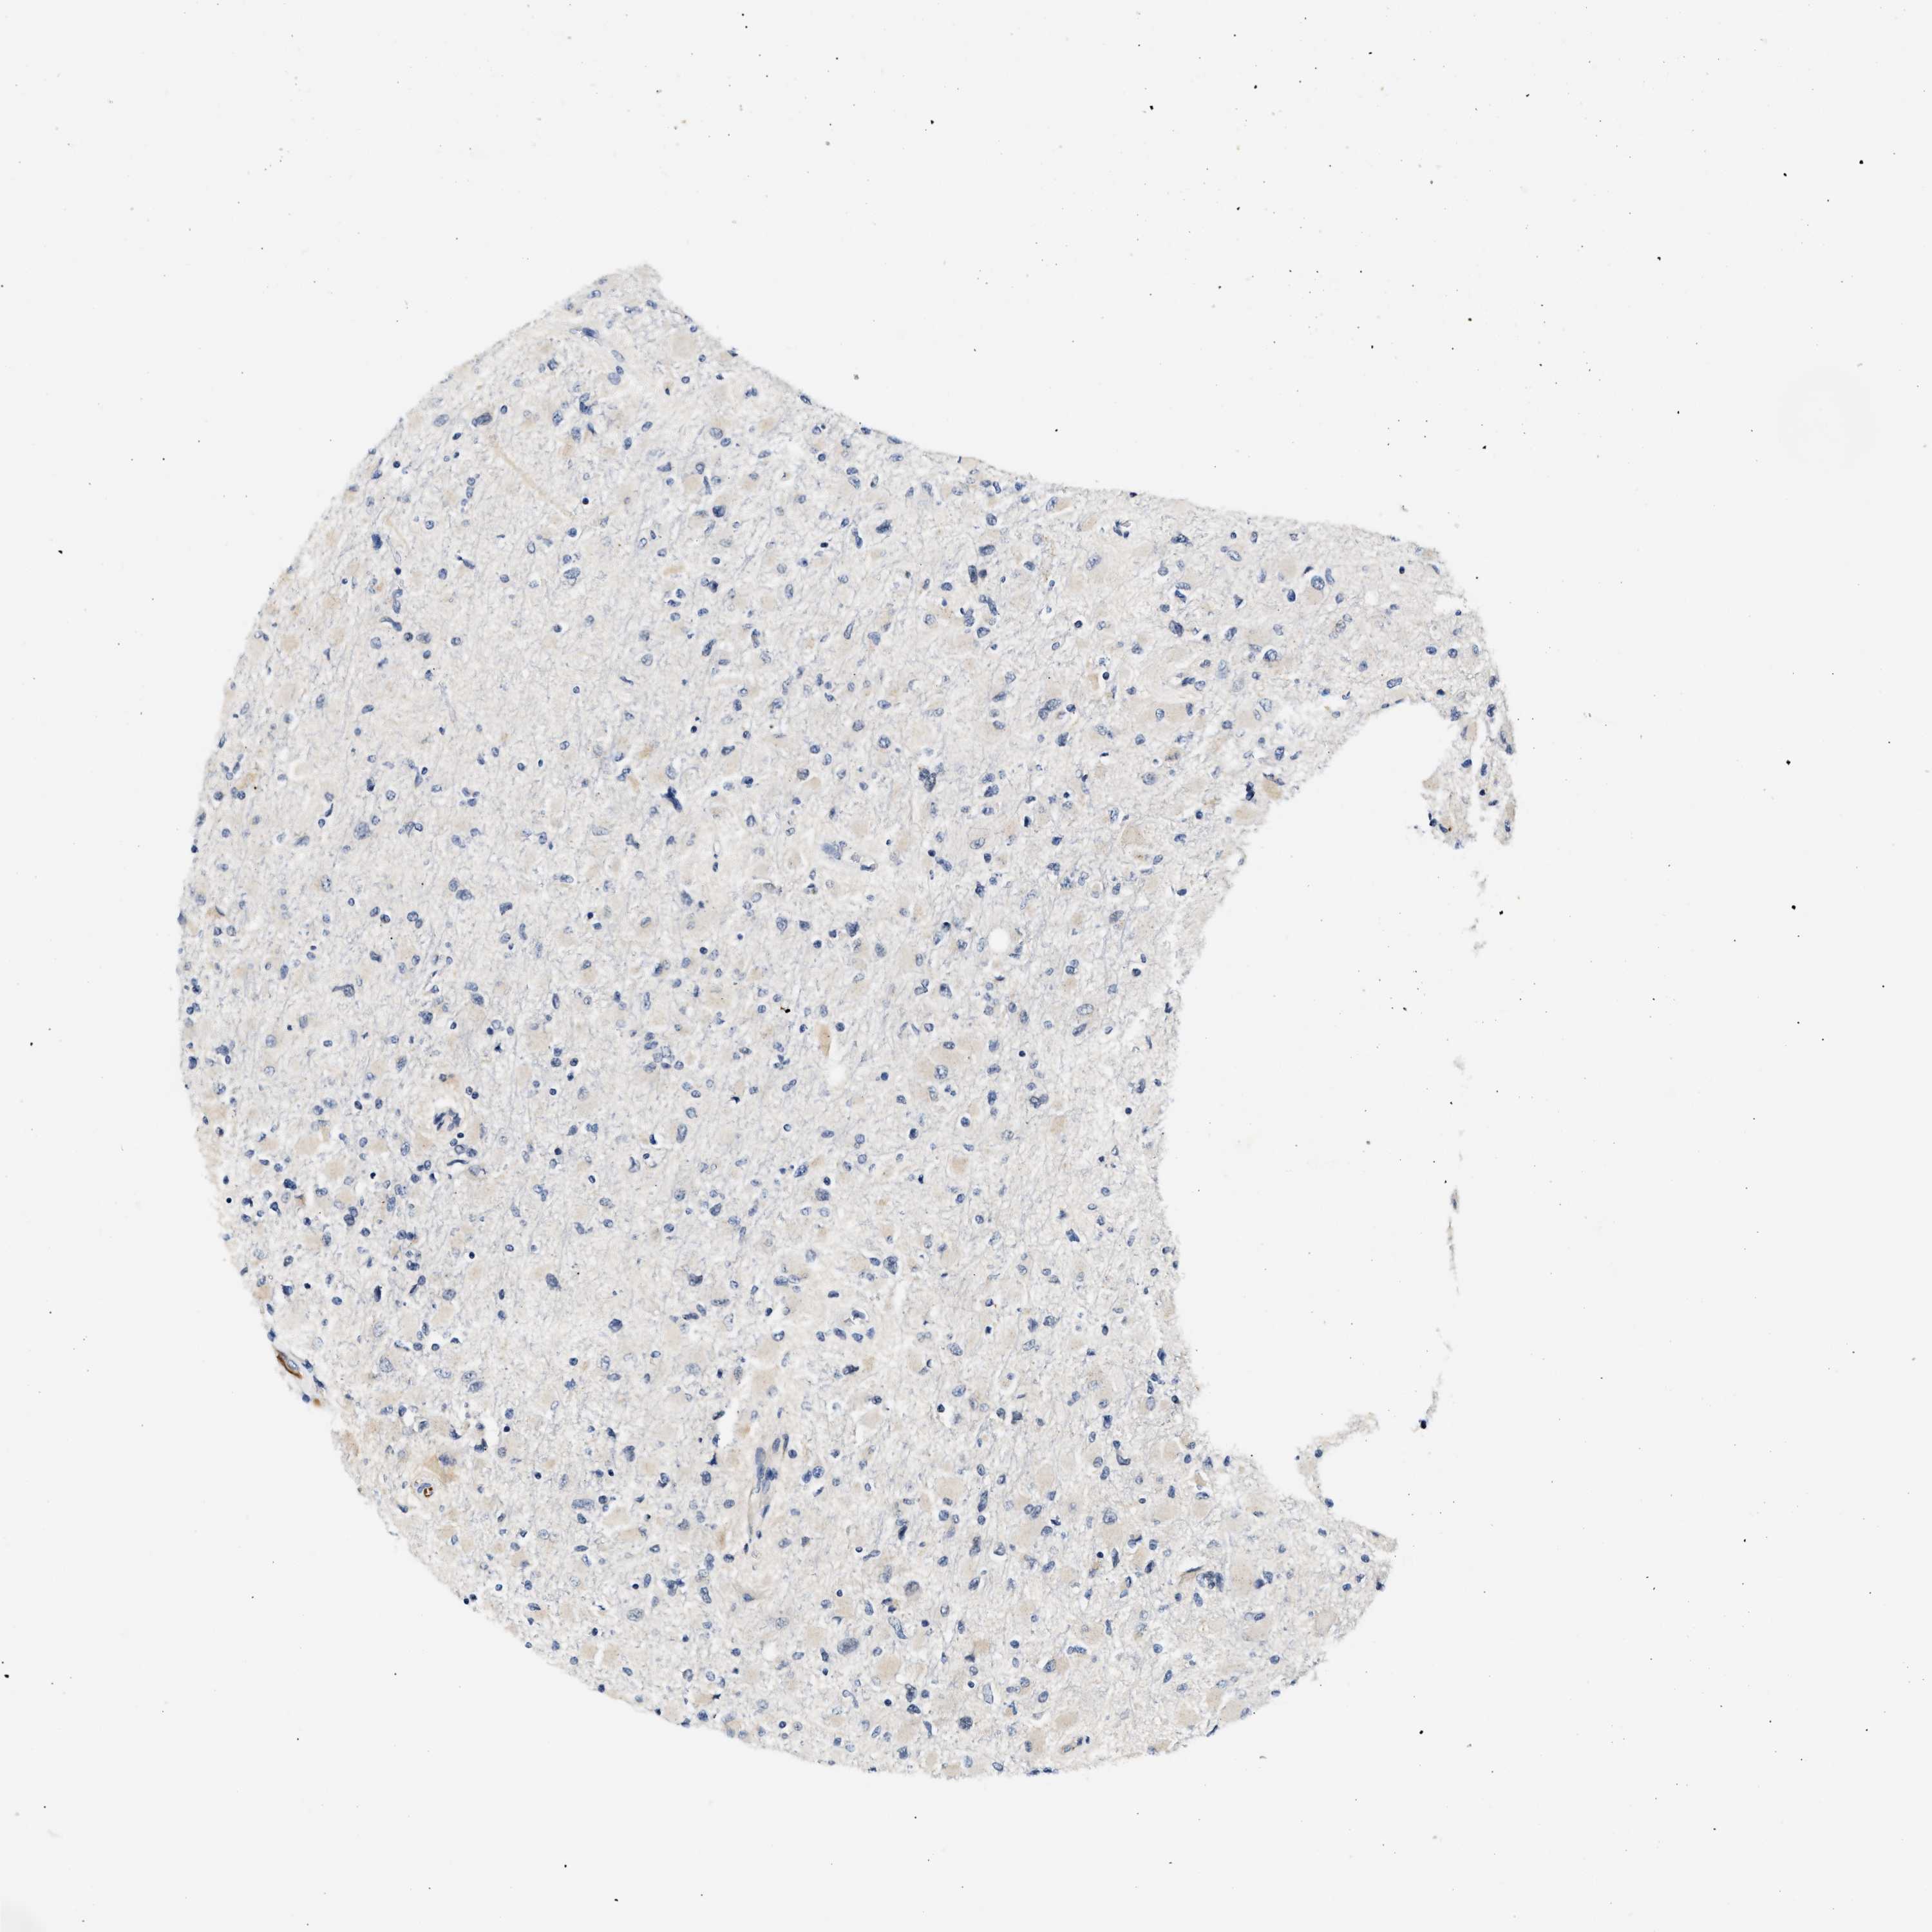

GLIOMA - Protein expressioni

A mouse-over function shows sample information and annotation data. Click on an image to view it in a full screen mode. Samples can be filtered based on level of antibody staining by selecting one or several of the following categories: high, medium, low and not detected. The assay and annotation is described here.

Note that samples used for immunohistochemistry by the Human Protein Atlas do not correspond to samples in the TCGA dataset.

Antibody stainingi

Antibody staining in the annotated cell types in the current human tissue is reported as not detected, low, medium, or high, based on conventional immunohistochemistry profiling in selected tissues. This score is based on the combination of the staining intensity and fraction of stained cells.

Each image is clickable and will lead to virtual microscopy that enables deeper exploration of all samples and also displays staining intensity scores, fraction scores and subcellular localization as well as patient and tissue information for each sample.

Antibody HPA020391

Staining

High

Medium

Low

Not detected

Intensity

Strong

Moderate

Weak

Negative

Quantity

>75%

75%-25%

<25%

None

Location

Nuclear

Cytoplasmic/membranous

Cytoplasmic/membranous,nuclear

Glioma, malignant, High grade

Glioma, malignant, Low grade